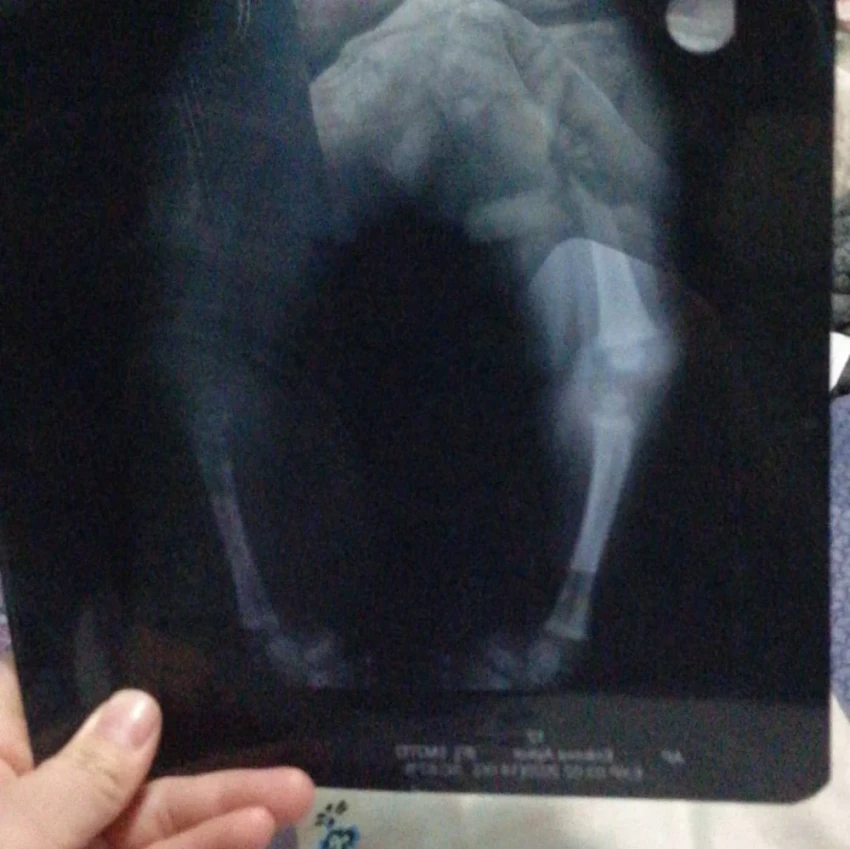

Aykol has already undergone two surgeries in Bishkek aimed at correcting the bilateral ankle joint deformity, but unfortunately, the results have been unsatisfactory.

“I learned that abroad there is an opportunity to perform a more complex and effective surgery. I started gathering information and contacted doctors in Turkey, who assured me that in our case, it is possible to correct the clubfoot. The cost of the surgery is $25,000. But I don’t know how I will be able to raise such an amount,” says Begimai.